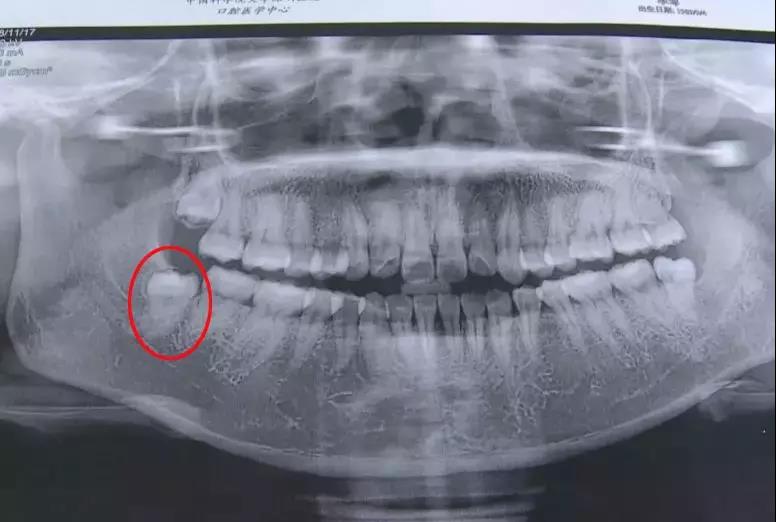

李女士因为智牙疼痛来到中国科学院大学深圳医院口腔科,医生经过一番检查之后,做了智齿拔除手术,共花费了一千多元。

记者通过采访医生得知,她长的这颗智齿比一般的智齿拔起来困难得多,因为她的这颗智牙需要做很多项检查和护理,也多了很多步骤,所以这个收费也是按照标准收取的。

1.2 恰当检查 包括高质量的X线片,它不仅能提供牙齿的清晰图像,牙根的轮廓和解剖以及牙周骨质情况,还能提供牙齿与邻牙和其他结构之间的关系,其中尤其是下颌骨下缘、下颌骨升支以及下牙槽神经束之间的关系。